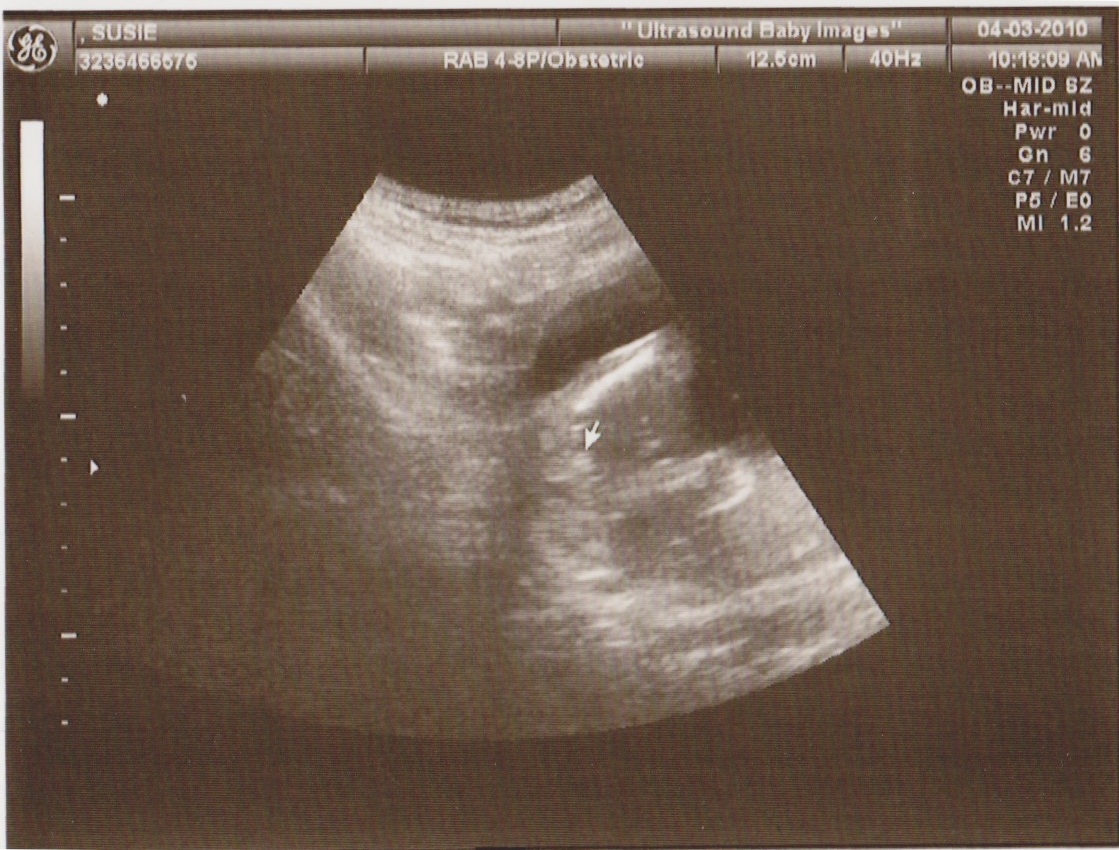

Well, as far as we know so far, it’s a GIRL! We just went today to a private 3D ultrasound facility that showed us (4 times) evidence that we have a girl on the way – see tiny arrow pointing to “lines” in the picture. In all honesty, it’s hard to tell what parts are doing what in there to me, but I suppose that’s why people get paid to do ultrasounds (and why no one’s paying ME to do that)…